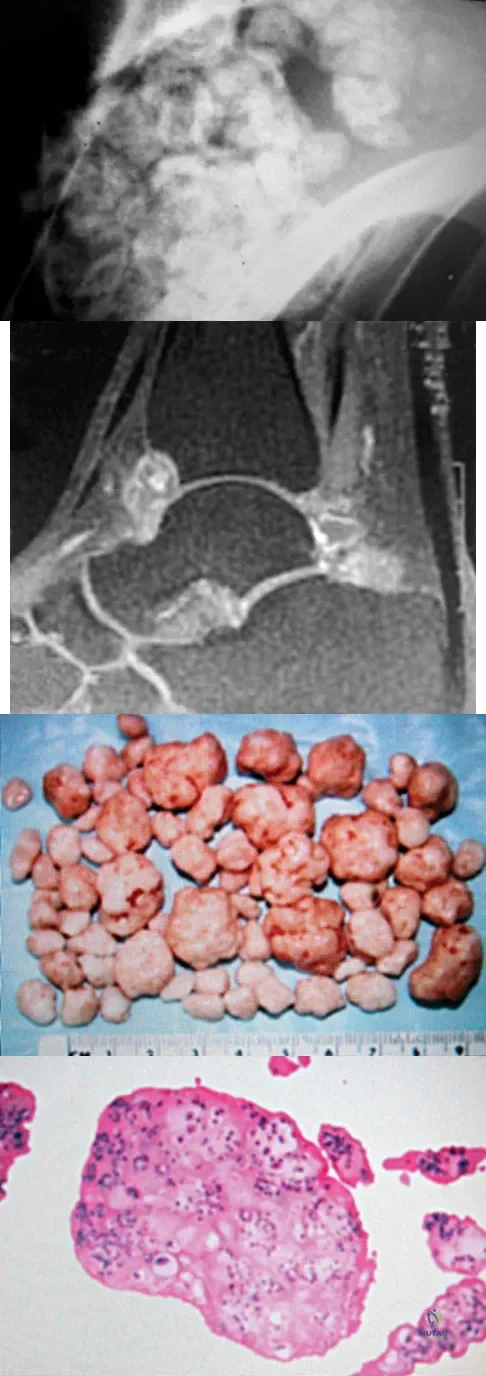

A 40-year-old man has a painful mass on his anterior ankle joint with limited range of motion. A radiograph, MRI scan, a gross specimen, and a hematoxylin/eosin biopsy specimen are shown in Figures 5a through 5d. What is the most likely diagnosis?

A 30-year-old patient has wrist pain. A radiograph and biopsy specimen are shown in Figures 34a and 34b. What is the most likely diagnosis?